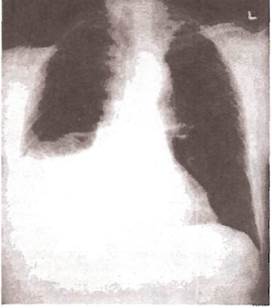

Рис. 23. Рентгенограмма легких при экссудативном плеврите и умеренном количестве плевральной жидкости.

Заметно интенсивное затемнение нижнего легочного поля слева, небольшое увеличение левой половины грудной клетки. Смещение средостения отсутствует

Рис. 25. Рентгенограмма легких больного с правосторонним экссудативным плевритом